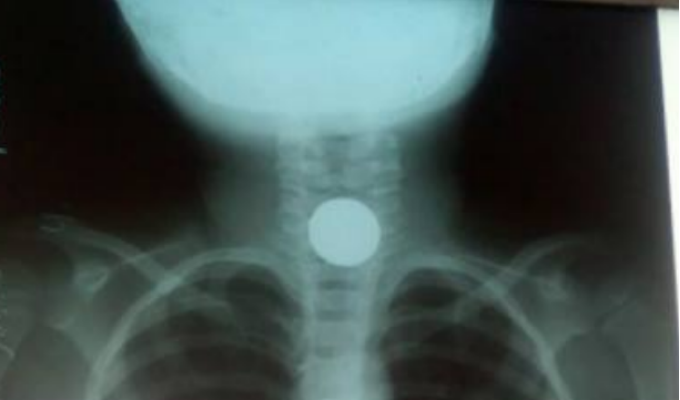

En un descuido, una menor de apenas cuatro años cogió una moneda de cincuenta céntimos y la ingirió, quedando atascada en la parte de su faringe. Ahora, ella se encuentra en estado crítico a la espera de las atenciones médicas en el estado ‘Santa Gema’ en Yurimaguas.